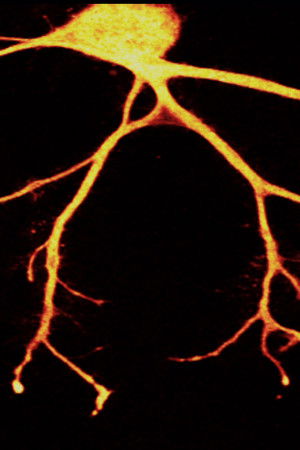

"In Search of Memory" is a very personal portrait of Eric Kandel, the "rock star" of neuroscience and the most important brain researcher of the 20th century. A fascinating documentary about the exciting mystery of the brain which arouses a curiosity in life and learning.